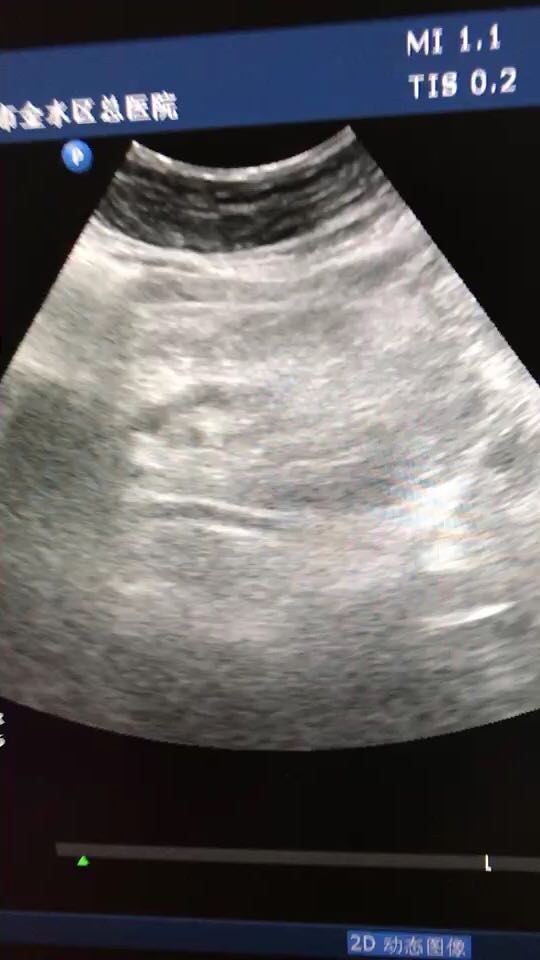

胰腺体积大

患者体检发现

查体 辅查

建议结合临床及其他相关实验室检查